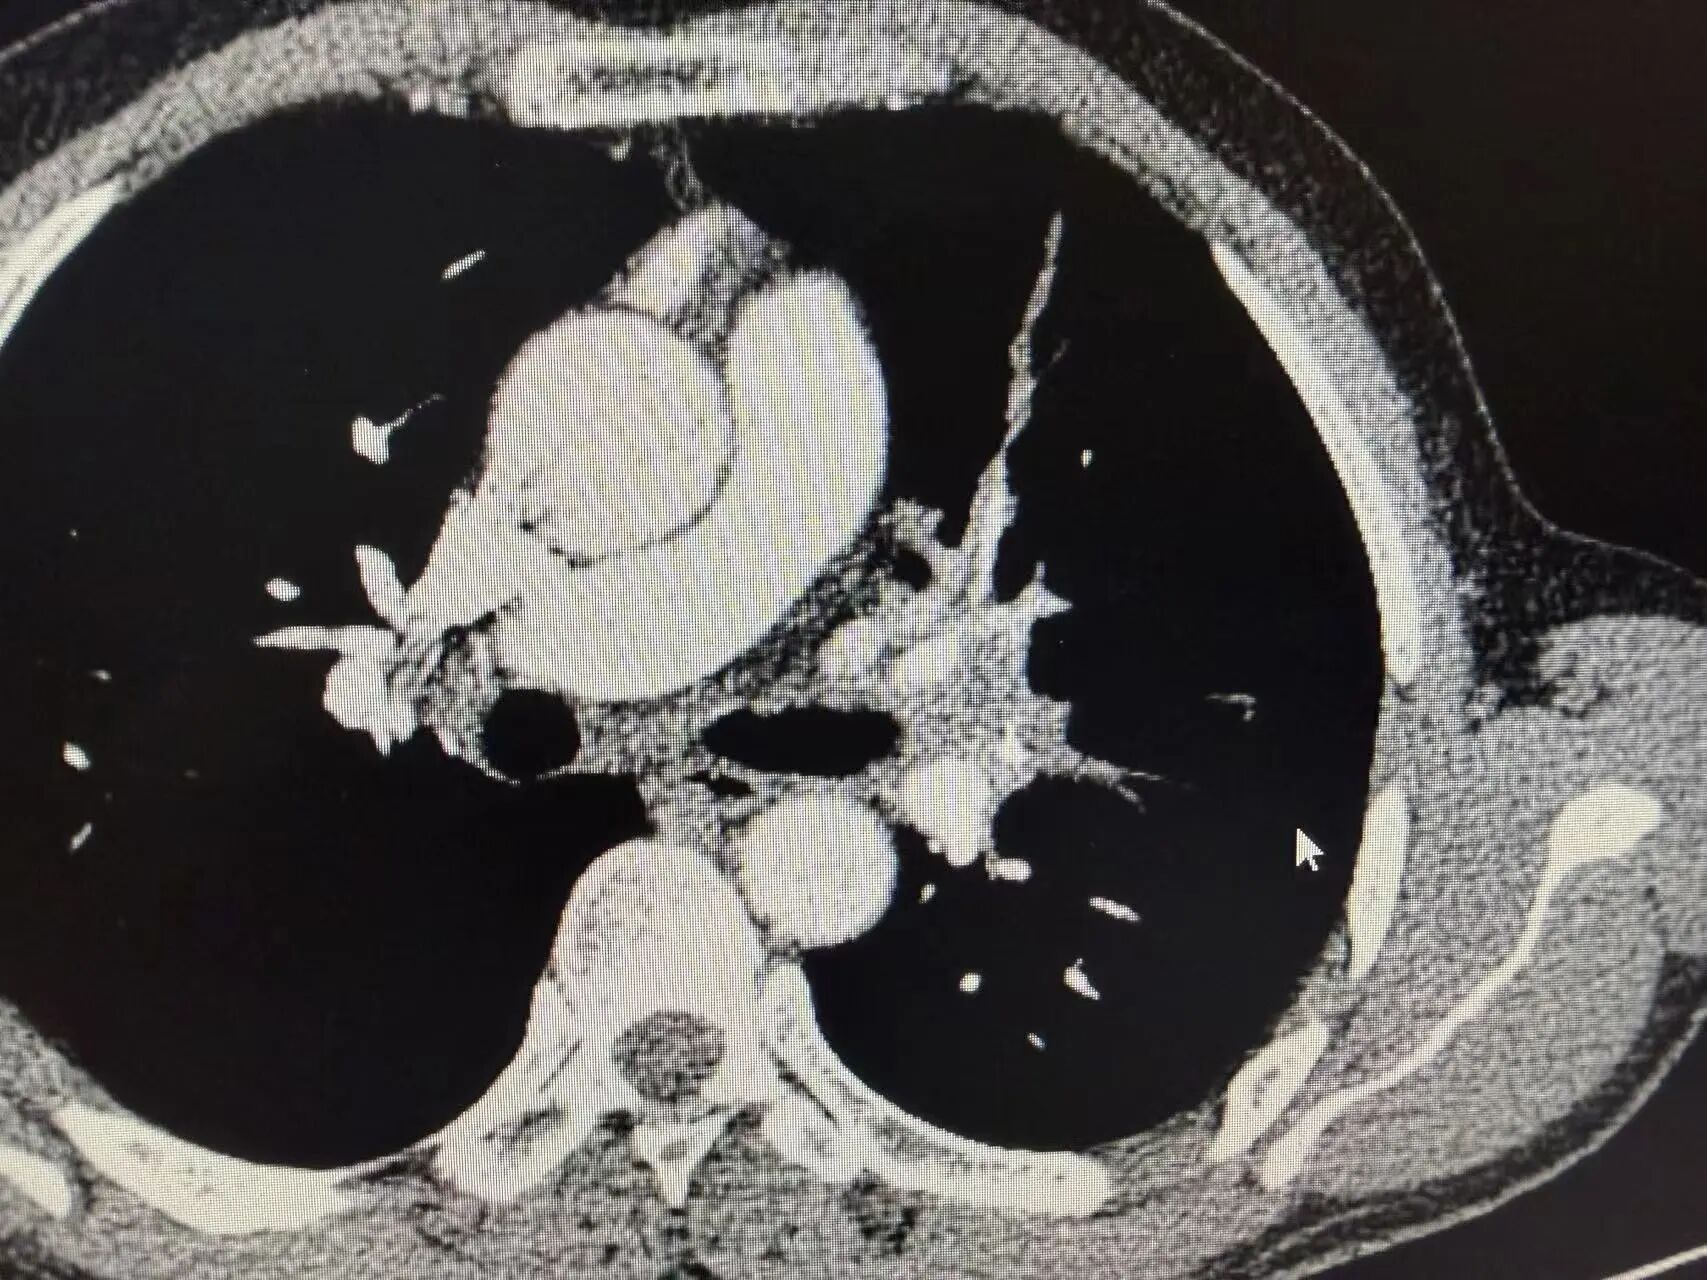

几个周期的治疗结束后,复查CT的结果传来了好消息:肿瘤明显缩小,原本粘连的血管也逐渐松动!这意味着,王叔终于获得了宝贵的手术机会,曾经的“不可切”,如今变成了“可切”。

新辅助治疗后CT:肿瘤明显缩小